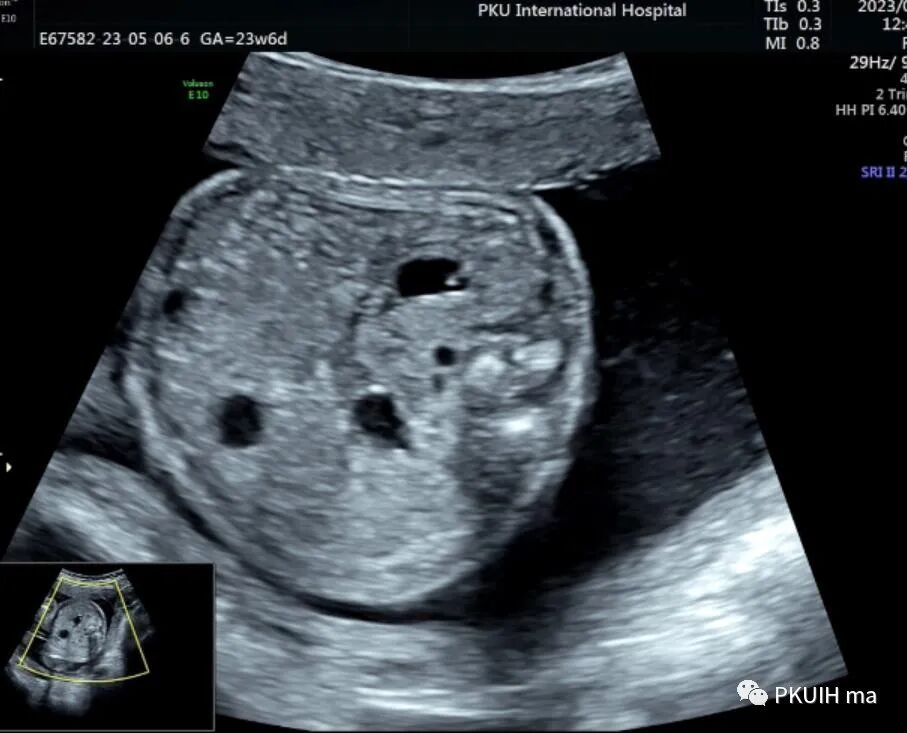

今天跟大家分享一个马蹄肾胎儿,23周常规系统排畸,矢状切发现胎儿肾脏偏长,下极边界相对不清晰,横断面发现肾盂有点轻度分离,但肾盂分离的方向有点不对劲,随仔细观察胎儿双肾。

矢状面肾下极轮廓不清,肾的位置相对偏低